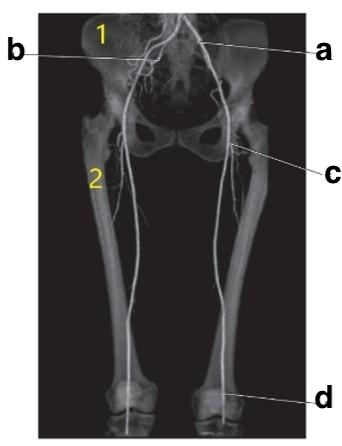

lesser trochanter

What structure cushions the articulation between the femoral condyles and the tibial plateaus?

The femoral artery is an extension of which artery?

External iliac

What anatomy is letter B?

Greater trochanter

Number 2 is on the __________ side of the patient.

lateral

Where is the tibial plateau?

3 and 4

What anatomy is # 2?

Ulna